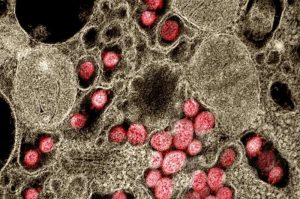

SARS-CoV-2: scoperti serbatoi virali

Uno studio ha scoperto che il virus SARS-CoV-2 può rimanere nei polmoni fino a 18 mesi dopo l’infezione, sfidando l’idea…

COVID-19: la persistenza di SARS-CoV-2 nei polmoni e il ruolo dell’immunità innata

COVID-19-Immagine Credit Public domain- Dall’Istituto Pasteur Lo studio ha dimostrato che il virus SARS-CoV-2 viene trasmesso da un macrofago all’altro…